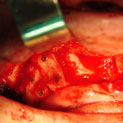

Existen muchas situaciones donde la pérdida y la atrofia ósea son tan graves que nos obligan a recurrir a la cresta iliaca del paciente, para conseguir el volumen óseo necesario para la correcta reconstrucción del maxilar. Así, la colocación de implantes será posible a los 3 meses.